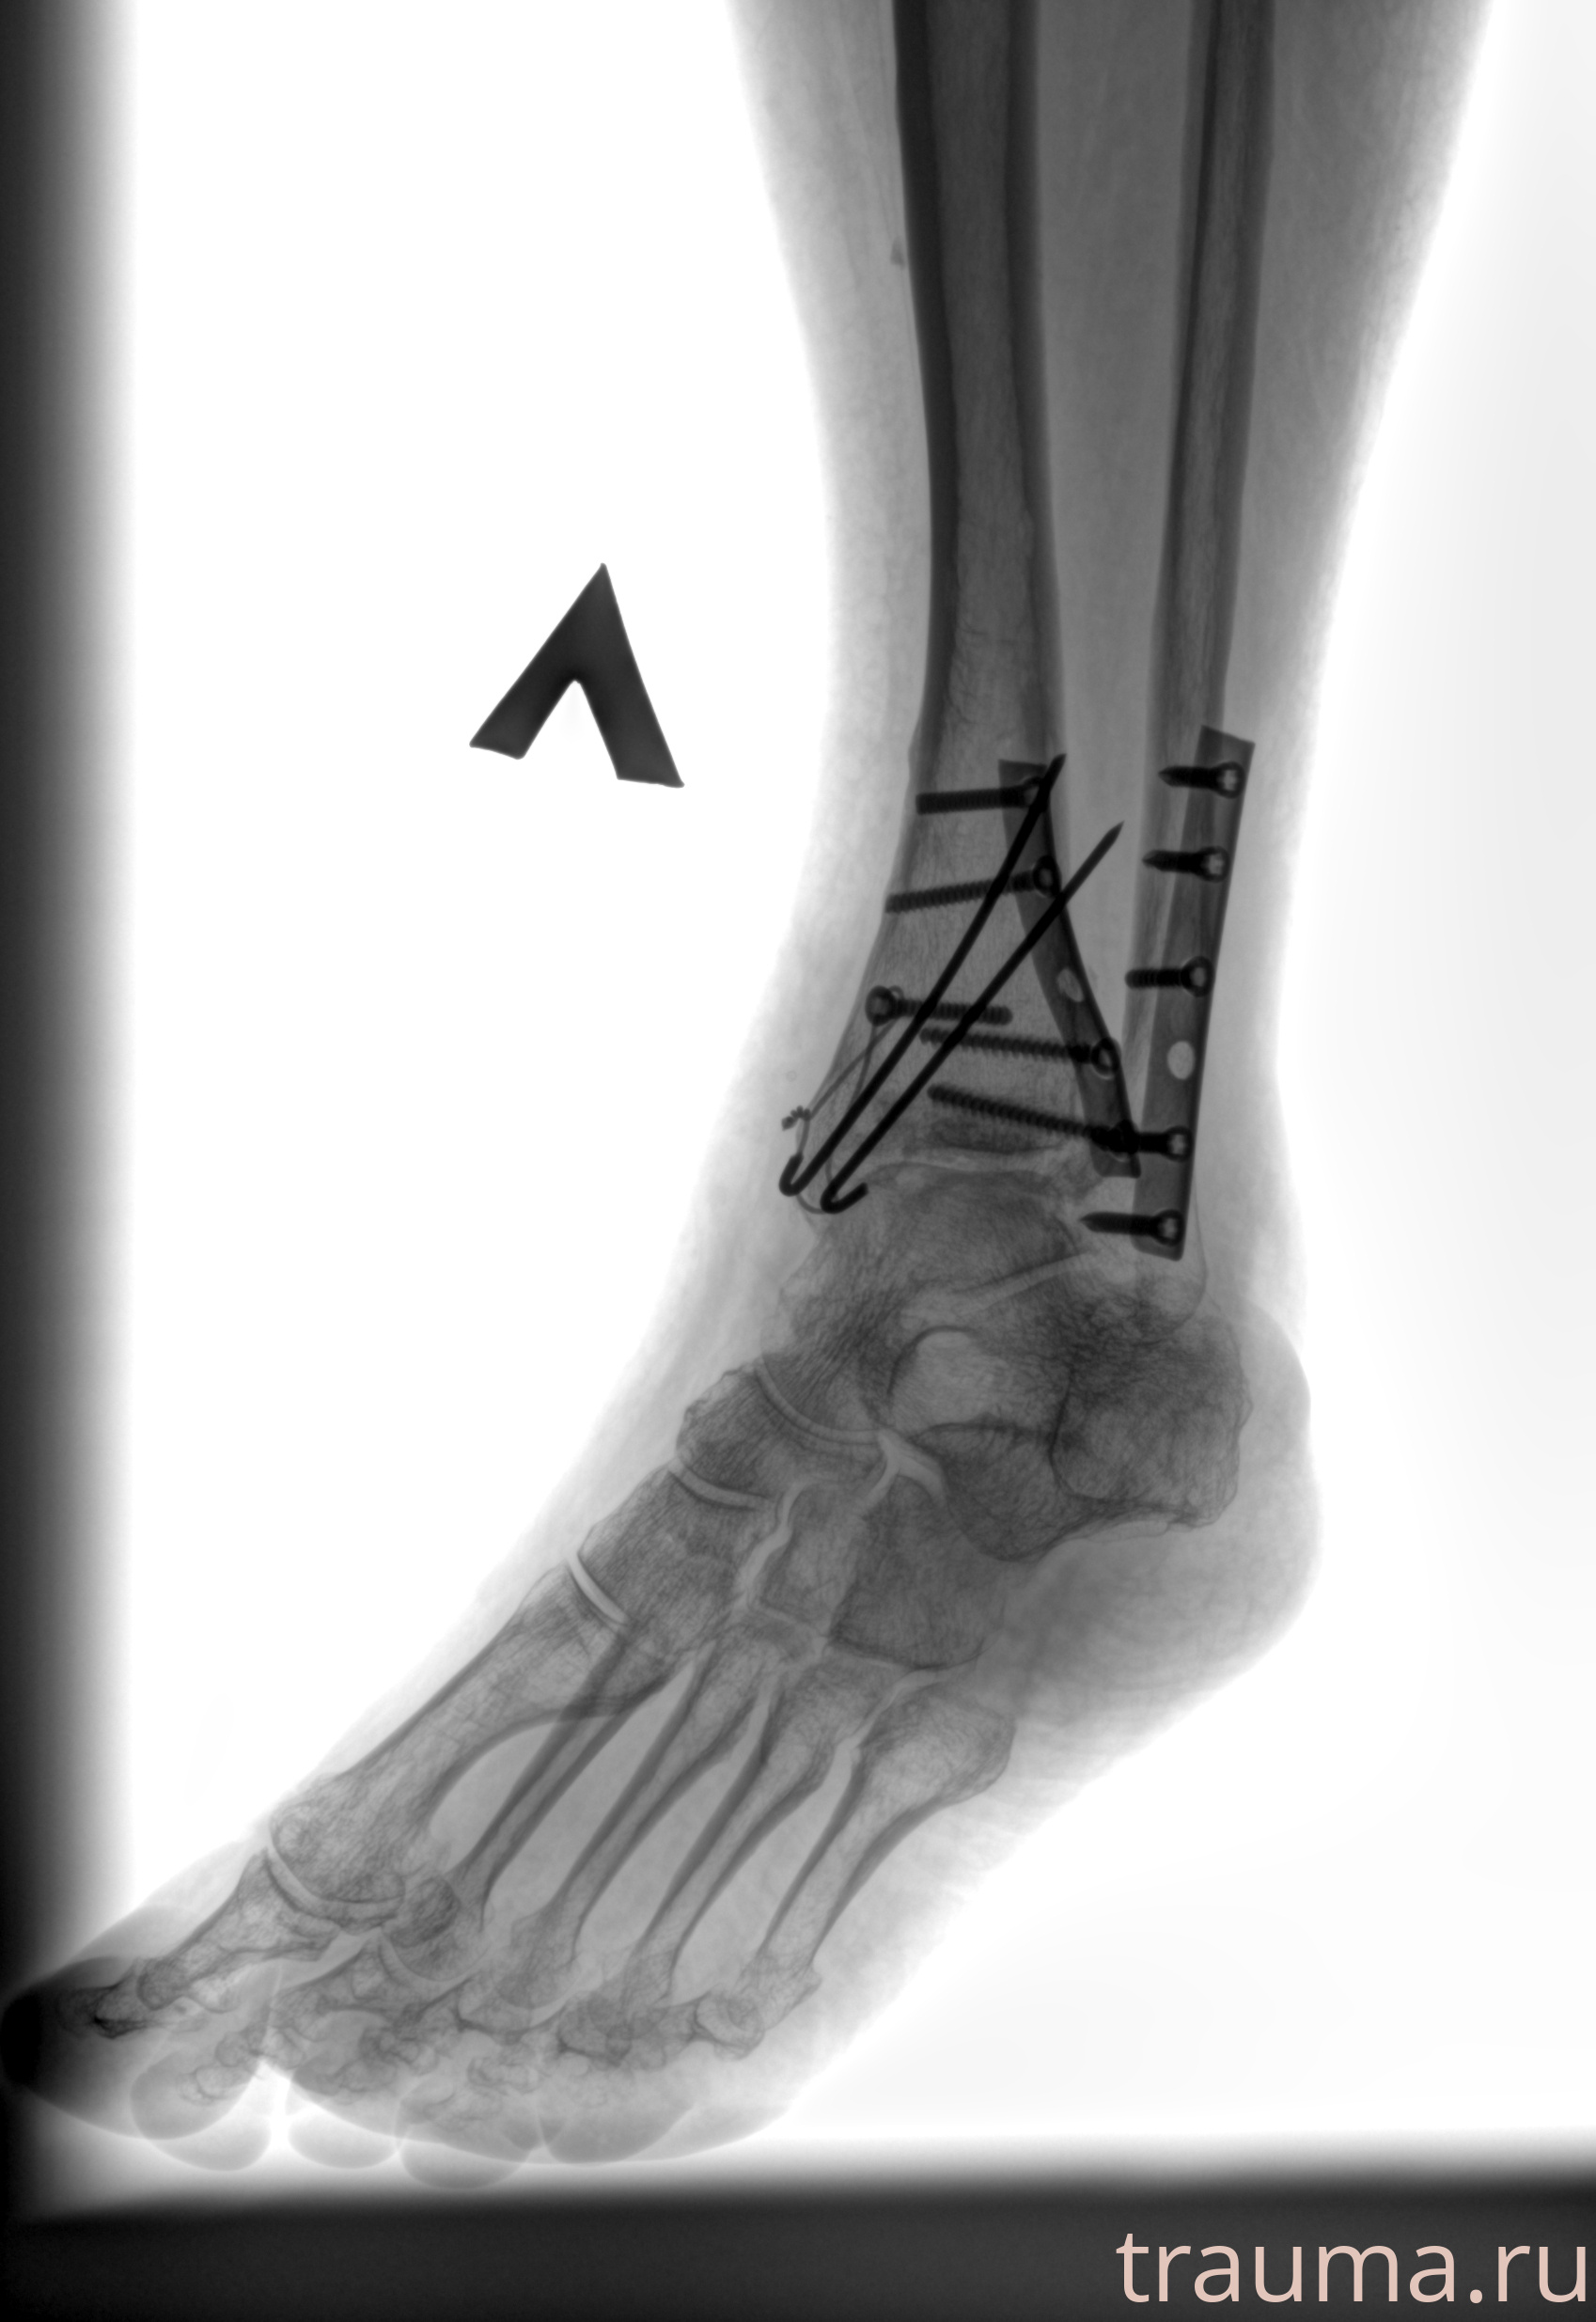

Рентген на дому: по вашему адресу приезжает врач-рентгенолог, травматолог-ортопед с мобильным рентгеновским аппаратом, проводит диагностику травмы или заболевания, делает необходимые рентгенограммы, дает рекомендации по дальнейшему лечению. Получить качественные снимки в домашних условиях возможно благодаря уникальной методике, разработанной МосРентген Центром для института  Склифосовского